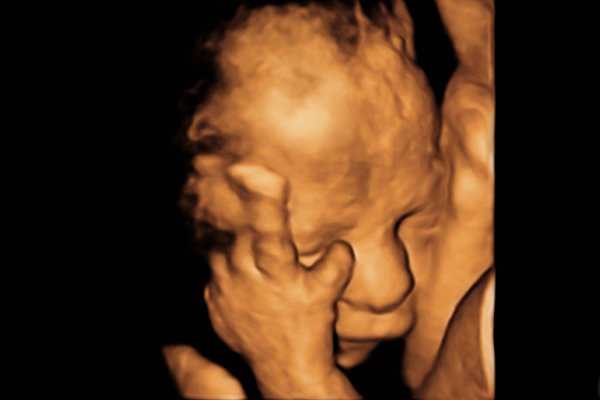

Gebelik sürecinde bebeğinizin gelişimini takip etmek en büyük heyecanınızdır. 3 boyutlu ultrason (3D) ve 4 boyutlu ultrason (4D), bu heyecanı bir adım öteye taşıyarak bebeğinizin yüz hatlarını ve hare...